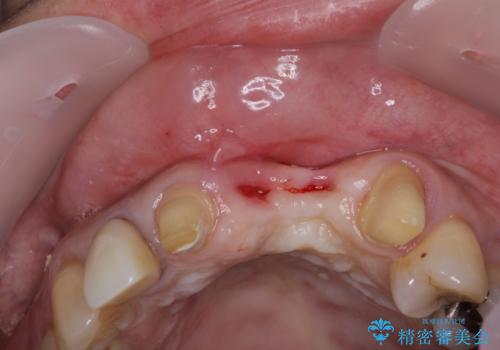

前歯は抜歯が必要であったので、抜歯を行い、その後歯肉移植をおこなった上でオールセラミックブリッジによる補綴治療を行うこととしました。